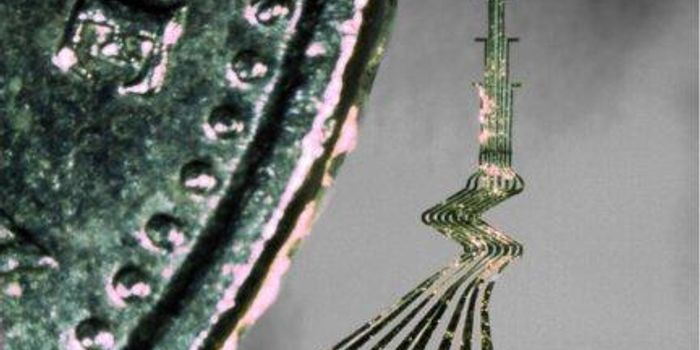

APR 15, 2016Clinical & Molecular DXImagine pouring a cup of coffee, stirring it, and lifting the cup to drink. Sounds simple for most people, but being abl ...

APR 12, 2016Clinical & Molecular DXNot unlike technology straight out of science fiction, scientists at the University of California, Berkeley have develop ...

MAR 03, 2016NeuroscienceAs a result of the war in the Middle East, there are 1,558 American soldiers who have suffered the loss of a limb. Add t ...

FEB 15, 2016NeuroscienceNormally when there is talk of a small piece of metal that can be implanted in the brain to take over the control of som ...